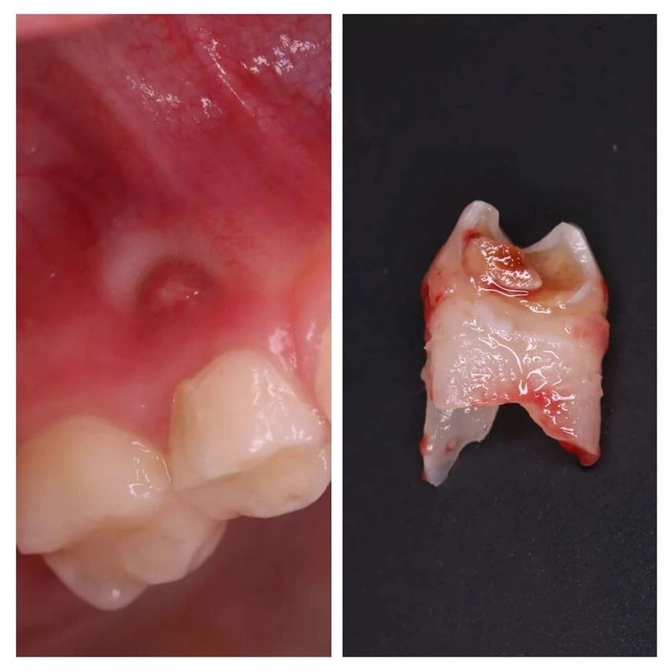

К сожалению, четвертый зуб пришлось удалить.

Видите "прыщик" над десной?

Это свищевой ход или попросту свищ.

Молочная "четверка" ранее была пролечена, но снова поражена кариесом.

Диагноз - периодонтит молочного зуба.

Именно из-за него на десне вылез свищ.

И это абсолютное показание для удаления.

Под местной анестезией зубик был удален.